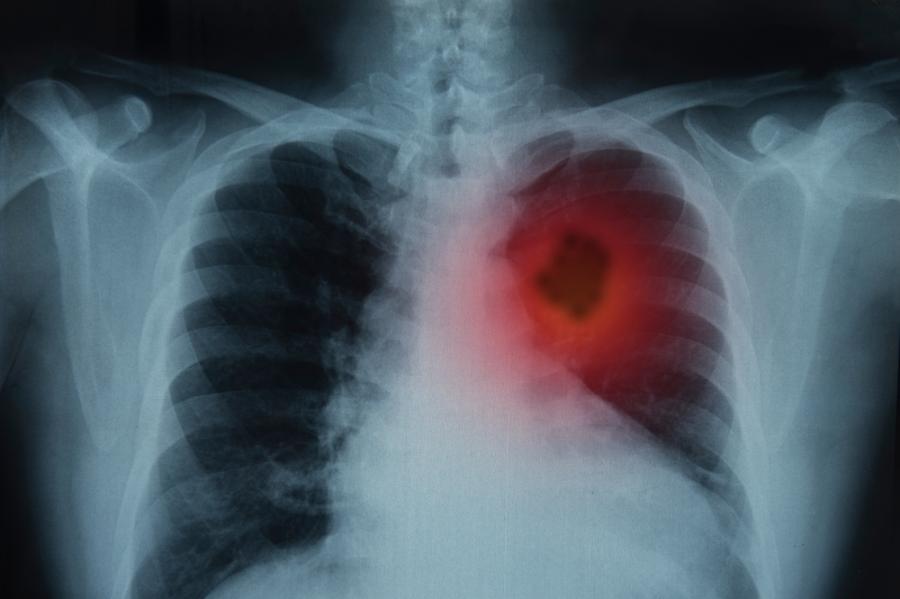

Ракът на белия дроб е сред петте най-често срещани видове рак

Ракът на белия дроб е сред петте най-често срещани видове рак в страната както сред мъжете, така и сред жените. Това сочат последните данни на Световната здравна организация (СЗО) от 2020 г. Проучване на Международната агенция за изследване на рака показва, че за същия период новодиагностицираните случаи на рак на белия дроб в България са 4300 – 5.6% от новодиагностицираните в Европа, а смъртните случаи са 3609, предава БНР. Данните бяха представени при откриването на втората за тази година Национална конференция по онкология на тема: „Карцином на бял дроб. Малигнен меланом”, организирана от Българското онкологично научно дружество.